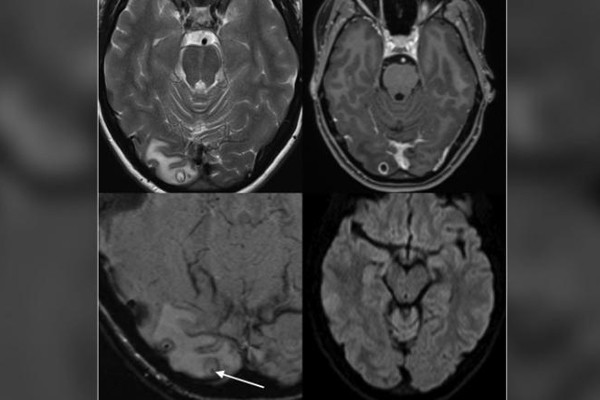

Cô gái đau đầu nhiều năm do có tổ sán trong não

Cô gái trẻ đến viện trong tình trạng đau đầu dữ dội, khi bác sĩ phẫu thuật bóc u não, phát hiện bên trong đầy sán.